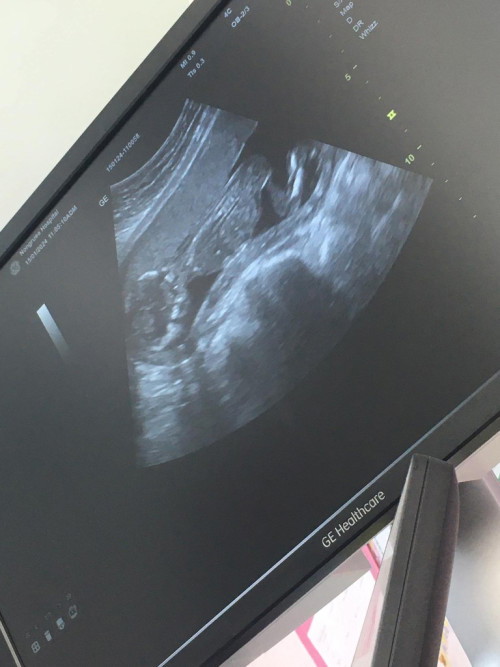

ลูกชาย 30+5w แล้ว ยังชอบปิดหน้าเวลาแม่พาไปหาคุณหมอ ไม่ยอมให้แม่เห็นหน้าเต็มๆสักทีเลย🫣